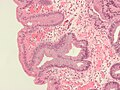

Barrettov jednjak označava prisutnost cilindričnog epitela u donjem dijelu jednjaka koji zamjenjuje normalni višeslojni pločasti epitel-tipičan je primjer za metaplaziju. Ovaj epitel koji nalikuje onome u želucu može bolje podnositi korozivno djelovanje želučane kiseline, međutim povećava opasnost od nastanka raka jednjaka.[7]

Imamo dva tipa metaplastičnih cilindričnih stanica: gastrične (želučane) koje su slične onima u želucu što se tehnički i ne smatra Barrettovim jednjakom i kolonične koje su nalik na epitel debelog crijeva. Obično se na biopsiji nađu oba tipa stanica. Metaplazija u kojoj stanice nalikuju onima iz debelog crijeva povezana je s genetski opterećenom populacijom.

Metaplazija je vidljiva na endoskopiji ali se uzorak mora pregledati mikroskopski da se utvrdi koji je tip stanica dominantan. Kolonička metaplazija je karakterizirana peharastim stanicama epitela i preduvjet je za postavljanje dijagnoze Barrettovog jednjaka.

Mikroskopska slika Barrettovog jednjaka. Alcian blue stain.